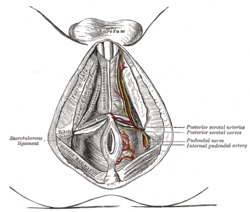

The superficial branches of the internal pudendal artery.